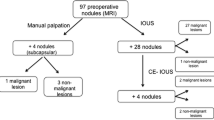

Surgery was performed under general anesthesia. After relaparotomy by reopening a Makuuchi incision, adhesions were cleared and palpation and ultrasound of the liver were performed. Nodules of the right lobe were palpable and visible within the ultrasound. In segment III, the suspicious nodule was then marked by a MRI-specific marker that is normally used for breast-specific MRI diagnostics (Bard® DuaLok ™). Rubber bands around the right hepatic vein, right hepatic artery, and right inflow pedicle were left in place. Surgical instruments and retractors were removed from the patient and the operative table.

Intraoperative MRI provided excellent images which demonstrated no suspicious liver lesions in the liver remnant (Fig. 6a and b). Retrospectively, the lesions seen on CT scan were likely due to the partial volume effect (Fig. 3). Consequently, no additional resection of segment II was necessary allowing completion of the ALPPS procedure as parenchymal sparing as planned. There were no relevant artifacts due to the open abdominal wall, the abdominal linen, or the sterile self-sticking sheet or rubber bands around the hepatic vessels.

Intraoperative ultrasound has been described to detect additional lesions not seen in preoperative CT scanning or MRI leading to a change of surgical strategy in 1.4% of cases [10]. The important role of the intraoperative ultrasound to detect lesions that have not been diagnosed in the preoperative MRI was once more confirmed in a recent paper in which is shown that the sensitivity of IOUS was superior to MRI (94.5% vs. 75.1%), with similar specificity. This paper showed that nodules located at the hepatic dome and lesions with mucinous histology are predictive factors for metastases missing at MRI. In this trial, the surgical plan was changed in 23% of patients due to intraoperative detection of new nodules [11].